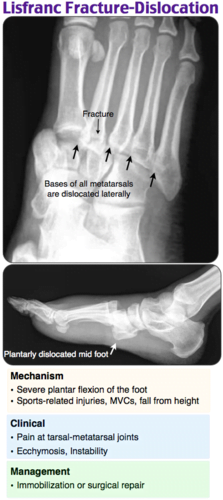

A x-ray of a human footDescription automatically generated